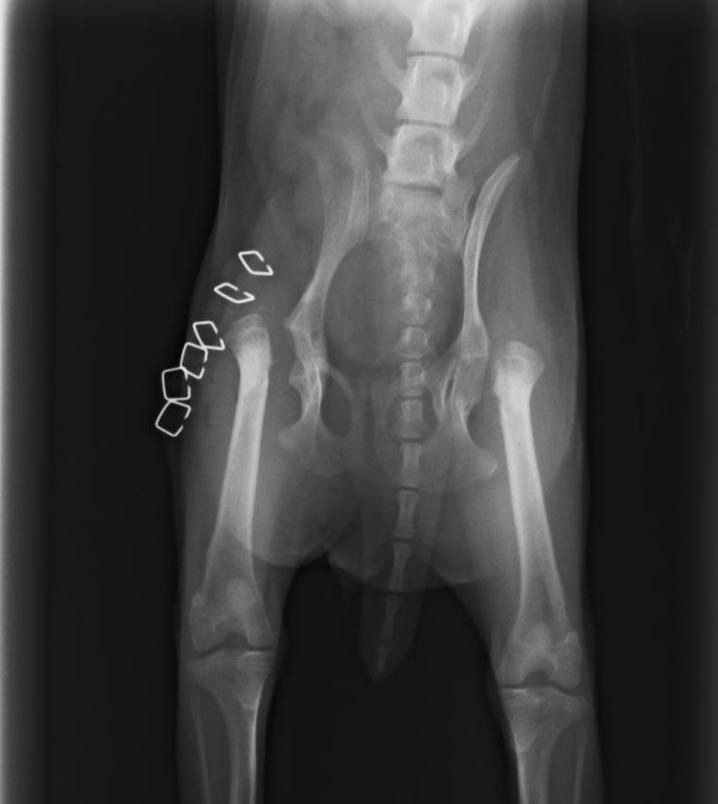

¿Necesitas radiografías oficiales de cadera?

Estamos acreditados para hacer las de cualquier raza

Displasia de cadera

Se trata de una enfermedad hereditaria, que se suele dar en razas como el pastor alemán, labrador, mastín, rottweiler, etc. Suele empezar a dar problemas a partir de los 7-8 meses de edad del cachorro, y es muy importante la detección precoz de la enfermedad.

El tratamiento puede ser

conservador, y si éste no funciona, pensar en un tratamiento quirúrgico. En este caso, cuanto antes hagamos la cirugía, mejor pronóstico va a tener nuestro perro.

Si lo que queremos es prevenir, es muy importante realizar radiografías si son de una raza predispuesta. Además, ofrecemos la posibilidad de realizar un Test Genético para labradores, mediante una muestra de sangre, y nos predice la capacidad de tener y transmitir la enfermedad a la descendencia.